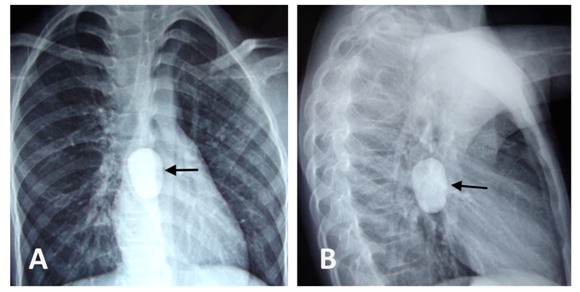

A 7-year old girl was referred to us with complain of absolute dysphagia. She had history of accidental pebble ingestion 13 days back. At the time of presentation, the child was conscious, dehydrated but had no respiratory distress. She was unable to swallow her saliva and she was complaining of retrosternal chest pain. A general physical examination was normal. A plain radiograph of the chest revealed a rounded radio-opaque object measuring around 2.5x3.5 cm located at the level of mid esophagus (Figure 1).

Figure 1 Chest X-Ray posterior-anterior view demonstrating radio-dense foreign body at the level of mid esophagus (A), Chest X-ray lateral view of the same patient (B).

Whenever a child presents with foreign body ingestion, a simple X-ray neck, chest and abdomen is recommended.3 It readily detects the radiopaque foreign bodies and sometimes may also diagnose associated complication like esophageal perforation. Radiographic contrast is usually avoided due to risk of aspiration. In few patients, in whom there is suspicion of esophageal perforation, computed tomography proves very useful in deciding the management plan [3]. In our case also, chest X-rays confirmed the presence and the location of the ingested FB (Figure 1).